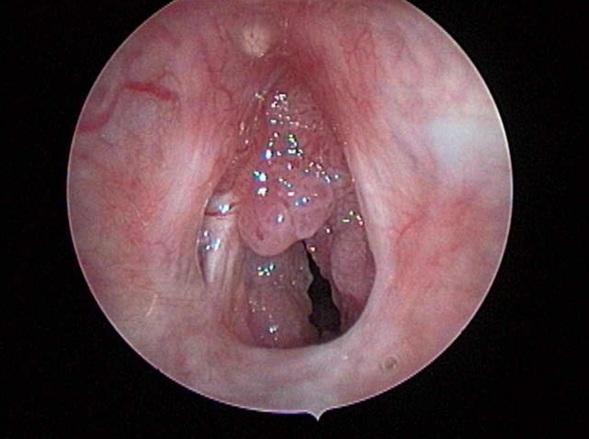

Nội soi họng: Khối papilloma màu hồng, dạng sùi nhiều thùy, bề mặt không chảy máu, chiếm gần trọn thanh môn.

Hình 3. Hình ảnh Papilloma trên nội soi